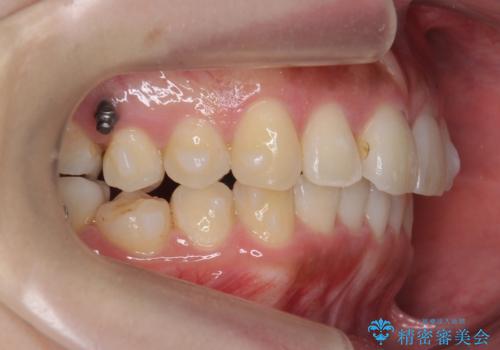

- 前歯のがたつきを主訴に来院。

前歯は目立つのでワイヤー矯正は絶対にしたくないとのことでした。

右上の奥歯を後ろに送り、前歯が出っ歯にならないように並べました。

また、右下の奥歯に一部目立たないように部分的なワイヤー矯正を行い、右下の奥歯が反対咬合になっていたのもしっかり中に入れて治療しています。

奥歯の反対咬合を治すのはインビザラインではかなり難しいのですが、しっかり治療できました。